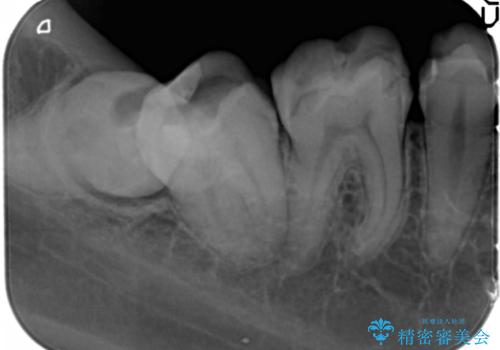

精査したところ、ほとんどの歯が保険内のレジンで充填されており、咬み合わせも悪く咬合していない歯もありました。

下顎の埋伏していた親知らずも抜去しました。